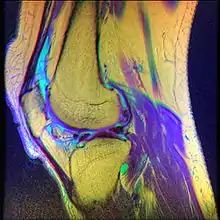

Diagnóstico e tratamento

O diagnóstico mais detalhado é feito, normalmente, através de um exame de Ressonância Magnética[28] e testes físicos realizados por fisioterapeutas,[6] além de fazer uma avaliação com um reumatologista, um fisiatra, um ortopedista, para receber o diagnóstico preciso e o tratamento correto.[29] Pode ser utilizado também, durante avaliação fisioterapêutica, escalas e testes funcionais para identificar o nível de impacto dessa dor e disfunção, no dia-a-dia do indivíduo.[30]